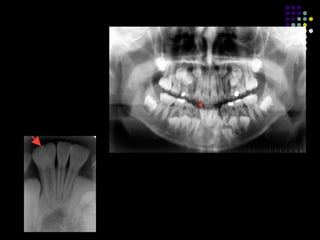

MESIODENS

Dientes supernumerarios

 Diente extra.

 Proliferacion continua de la lamina dental

primaria/permanente hasta formar un 3er germen.

 Morfologia normal/rudimentario/miniatura.

 Mayoria aislados.

 Otros sindromes asociados: Sindrome de Gardner,

 Displasia cleido craneal.

 Mas frecuente en denticion permanente.

 Mas frecuente en maxilar superior.

 Sitio mas comun: linea media anterior del maxilar

superior, mesiodens.

 Segundo sitio mas comun: area molar superior.

 Significado clinico: espacio.

 Impactados:

1. Bloquean la erupcion de otros dientes.

2. Erupcion retardada.

3. Erupcion defectuosa de dientes adyacentes.